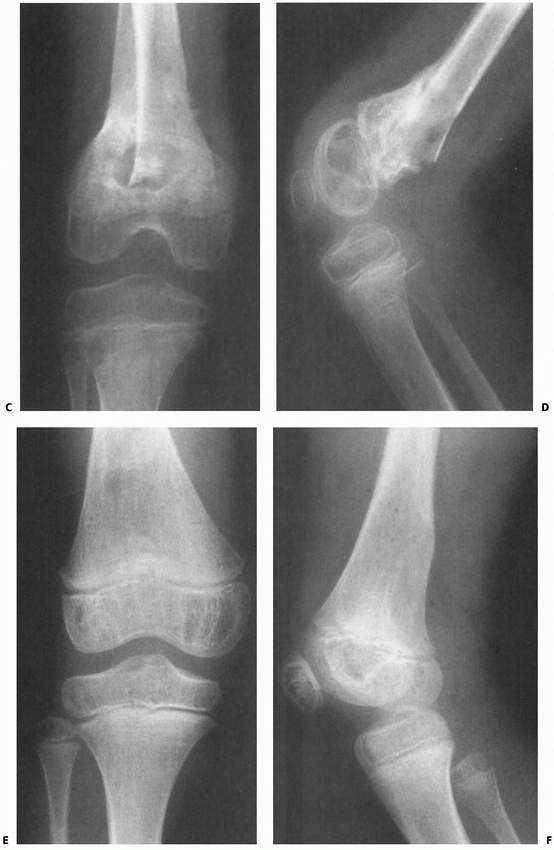

FIGURE 23-5 A.

Completely displaced Salter-Harris type II fracture of the distal femur in a 6-year-old girl whose foot was on the back of the driver’s headrest when the automobile in which she was riding was involved in an accident. B. Ecchymosis in the popliteal fossa and anterior displacement of the distal femur are evident. Clinical examination revealed absence of peroneal nerve function and a cold, pulseless foot. |

FIGURE 23-5 (continued)

The fracture was irreducible by closed methods and required open reduction, internal fixation, and repair of a popliteal artery laceration. C,D. Incomplete reduction Salter-Harris type II fracture in a 6-year-old girl with 25 degrees of posterior angulation and abundant callus formation. E,F. Four years later, remodeling has occurred and no growth disturbance is noted. Results such as this cannot be relied upon, and early anatomic reduction is recommended. |